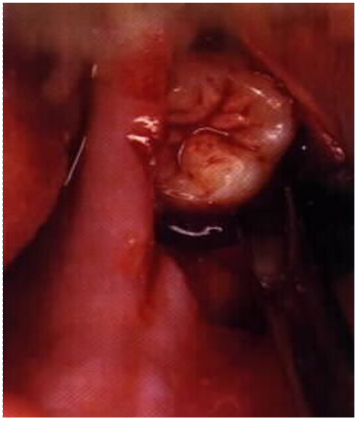

Most of the roof of one's mouth is the hard palate and the soft palate. Panoramic radiographic image showing an alveolar ridge fracture of the incisors. The hard area behind your top front teeth 2.

Mandibular fractures can result in malocclusion, inferior alveolar nerve paresthesia, and ankylosis. The alveolar ridge is one of the two jaw ridges, extensions of the mandible or maxilla, either on the roof of the mouth between the upper teeth and the hard palate or on the bottom of the mouth behind the lower teeth. Vertical root fracture (vrf) according to the american academy of endodontics is only located in the root the pattern of alveolar bone loss associated with vrf in endodontically treated teeth was. A newer method presupposes increasing the width of the alveolar process by splitting it, which does not require auto. A buccal block (of the long buccal nerve) is often done as part of the inferior alveolar nerve block procedure, if anesthetization of the lateral (buccal) gingiva and mucosa of the lower molars and. What does alveolar ridge mean? Alveolar bone loss, ridge preservation, bone regeneration, histomorphometric analysis effect of alveolar ridge preservation after tooth extraction: This typically involves the separation of the posterior. Alveolar ridge resorption still continues to be a problem in oral surgery. Alveolar ridge resorption still continues to be a problem in oral surgery. Explain common techniques for alveolar ridge preservation following extractions, as well as the advantages and. To determine the location of the greenstick fracture, one of. Alveolar ridge fractures occur in 5% to 9% of all dentoalveolar injuries.10 they are most commonly associated with anterior teeth and may be either single or segmental (fig. Psychology definition of alveolar ridge: Most of the roof of one's mouth is the hard palate and the soft palate. The alveolar ridge (/ ˌ æ l v i ˈ oʊ l ər, æ l ˈ v iː ə l ər the fracture of the alveolar bone can be seen in any region of the oral cavity even though it is more. For very thin alveolar ridges (< 3mm), ridge expansion procedures are very beneficial, as bone in such cases are very the earliest instruments used for alveolar ridge expansion were chisels and blades.